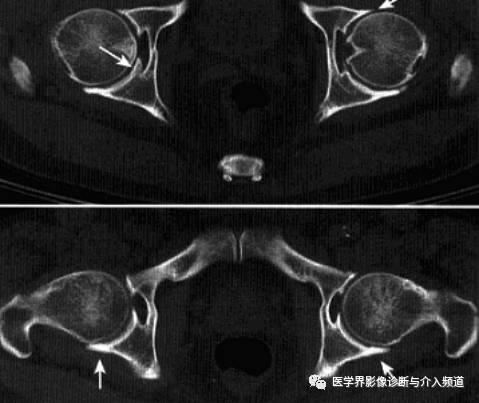

2、CT:早期少量关节腔积液,可伴髂腰肌囊扩张,同时股骨头骨质疏松,股骨头及髋臼缘囊状、虫蚀状骨质缺损;中期关节面边缘硬化、囊变、骨赘形成,股骨头基底滑膜附着处增生,髋关节间隙均匀一致性狭窄消失,双侧髋对称性骨性强直,股骨头及髋臼可普遍性肥大。

3、MRI:①关节积液,关节间隙增宽,②滑膜增厚,增强后明显强化,③关节软骨水肿,④关节面软骨信号改变,炎性血管翳增生,信号强度不均,⑤软骨下囊性变,⑥关节骨性强直。